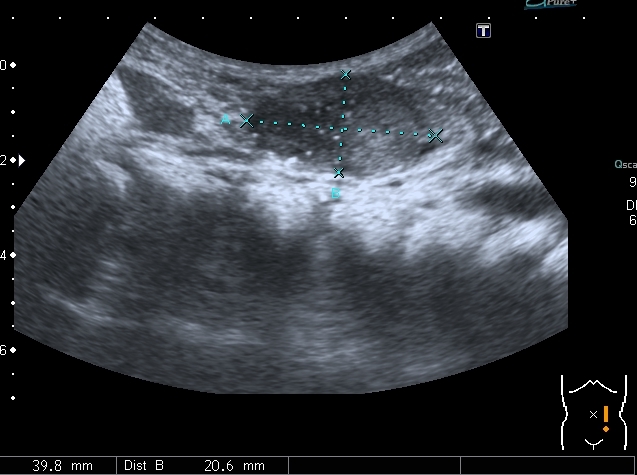

В хирургический приёмный покой поступил ребёнок 2-х лет с жалобами родителей на увеличение живота. Направлен на УЗИ с диагнозом "Опухоль Вильмса справа?"

При осмотре - живот увеличен в размерах, в правой половине пальпируется плотное образование.

При УЗИ вся правая половина живота выполнена солидно - кистозным образованием больших размеров.